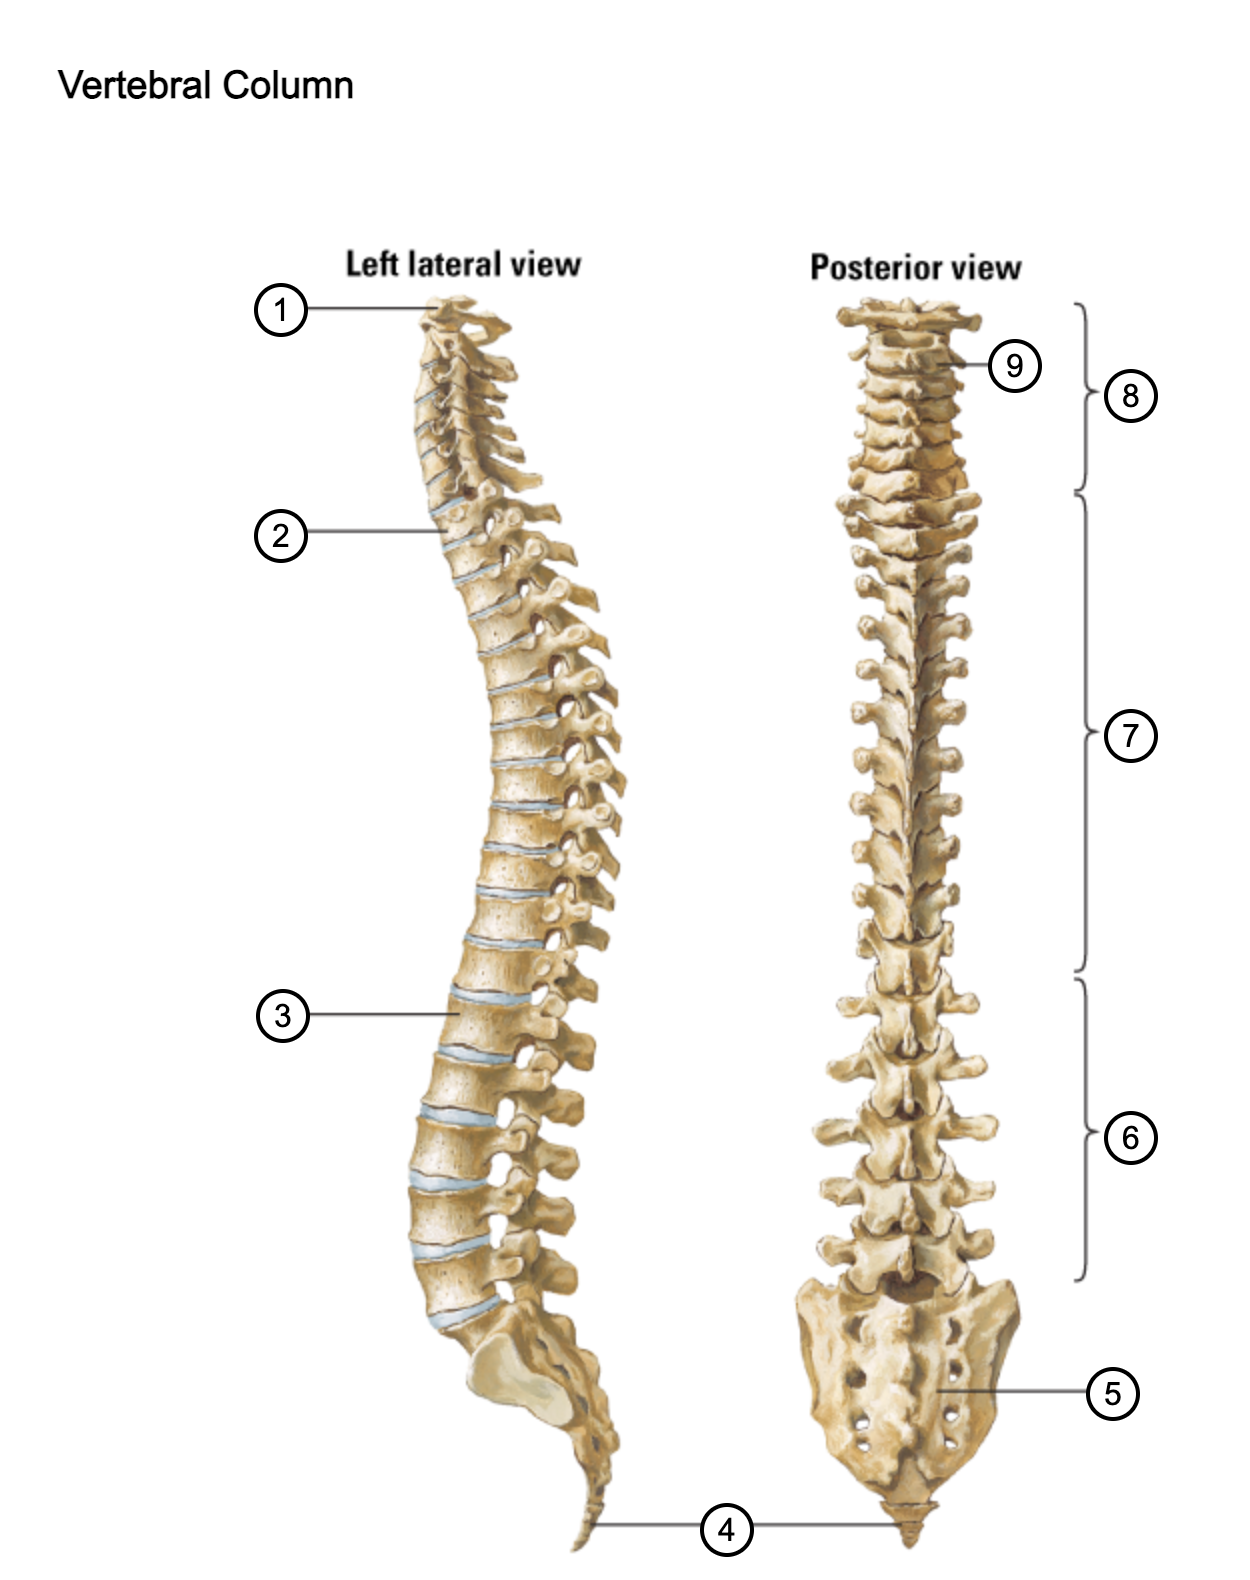

1

atlas (C1)

2

T1

3

L1

4

coccyx

5

sacrum (S1-5)

6

lumbar vertebrae

7

thoracic vertebrae

8

cervical vertebrae

9

axis (C2)